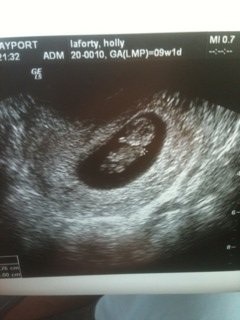

Hello ladies can someone please look at my ultrasound and tell me what u think the gender is based on ramzi theory? It was right with my last baby please!!! This is transvaginal at 6w3d and hr is 134